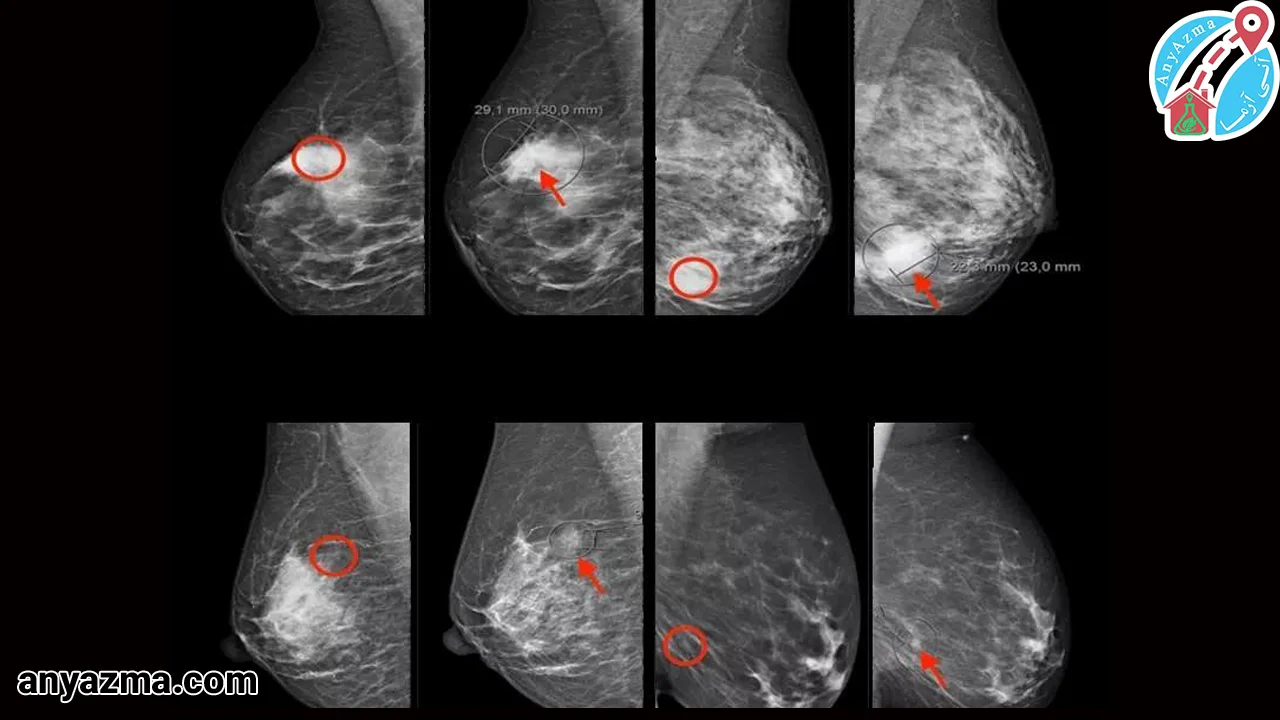

میتوان گفت سونوگرافی سینه یک نوع از آزمایش چکاپ برای تشخیص سرطان است که با امواج صوتی، تصاویری دقیق از بافتهای داخلی ارائه میدهد. این تکنیک بهویژه در شناسایی تومورهای مخفی و کمک به تشخیص زودهنگام نقش کلیدی دارد.

- شناسایی الگوهای غیرطبیعی: این روش تومورهای سرطانی را از طریق تودههای نامنظم یا تغییرات بافتی آشکار میکند.

- کارایی در بافت متراکم: در زنان با بافت متراکم سینه، سونوگرافی سرطانهایی را که در ماموگرافی پنهان ماندهاند، شناسایی میکند.

- دقت وابسته به اندازه تومور: تومورهای بزرگتر از 0.9 سانتیمتر با odds ratio2 شانس بیشتری برای تشخیص دارند.